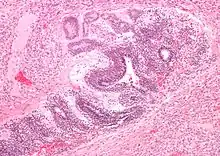

| Micrograph of the primitive neuroepithelium of an immature teratoma of the mediastinum. H&E stain. | |

A mediastinal tumor is a tumor in the mediastinum, the cavity that separates the lungs from the rest of the chest. It contains the heart, esophagus, trachea, thymus, and aorta. The most common mediastinal masses are neurogenic tumors (20% of mediastinal tumors), usually found in the posterior mediastinum, followed by thymoma (15–20%) located in the anterior mediastinum.[1] Lung cancer typically spreads to the lymph nodes in the mediastinum.

The mediastinum has three main parts: the anterior mediastinum (front), the middle mediastinum, and the posterior mediastinum (back). Masses in the anterior portion of the mediastinum can include thymoma, lymphoma, pheochromocytoma, germ cell tumors including teratoma, thyroid tissue, and parathyroid lesions. Masses in this area are more likely to be malignant than those in other compartments.[2][3]